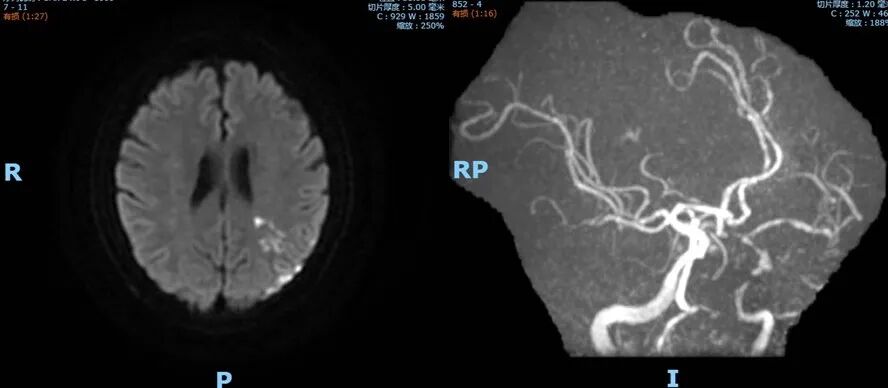

既往病史影像留存

2022-02-05 颅脑MR。

导丝怎么扩【载药时代 球扩天下】NOVA DES®颅内药物洗脱支架在颈内动脉颅内段重度狭窄的应用二例!_https://www.jmylbn.com_新闻资讯_第23张

DWI

导丝怎么扩【载药时代 球扩天下】NOVA DES®颅内药物洗脱支架在颈内动脉颅内段重度狭窄的应用二例!_https://www.jmylbn.com_新闻资讯_第24张

MRA

重要影像结论:左侧额顶枕叶梗死灶。

入院影像检查

2022-07-21 颅脑MR。

导丝怎么扩【载药时代 球扩天下】NOVA DES®颅内药物洗脱支架在颈内动脉颅内段重度狭窄的应用二例!_https://www.jmylbn.com_新闻资讯_第25张

导丝怎么扩【载药时代 球扩天下】NOVA DES®颅内药物洗脱支架在颈内动脉颅内段重度狭窄的应用二例!_https://www.jmylbn.com_新闻资讯_第26张

导丝怎么扩【载药时代 球扩天下】NOVA DES®颅内药物洗脱支架在颈内动脉颅内段重度狭窄的应用二例!_https://www.jmylbn.com_新闻资讯_第27张

DSA

重要影像结论:左侧颈内动脉C4段重度狭窄。